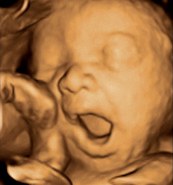

La evolución del feto a través de ecografías

Ecografía de 21 semanas: una ecografía en tres dimensiones puede aportar datos complementarios para poder observar bien el rostro del bebé. En la imagen, ¡el bebé está bostezando!